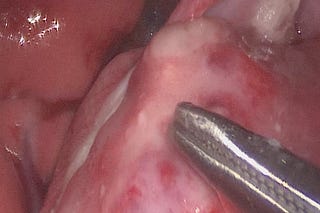

Fístula arterio-portal congénita en una gata

Póster sobre esta interesante anomalía vascular hepática en una gata